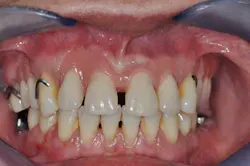

Figs. 8a, b, c, and d: Final results

- Final result.